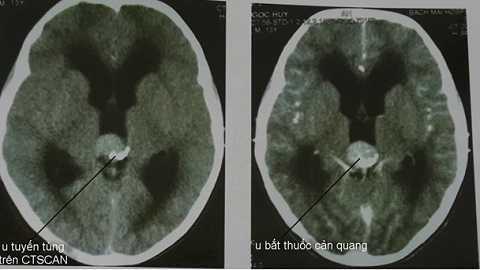

U tuyến tùng, cẩn thận nhầm bệnh tiêu hóa mà tử vong

(VTC News) – Bác sĩ cảnh báo người bị u tuyến tùng dễ bị nhầm lẫn với bệnh về tiêu hóa nên cần biết để đưa bệnh nhân khám sớm, tránh tử vong.